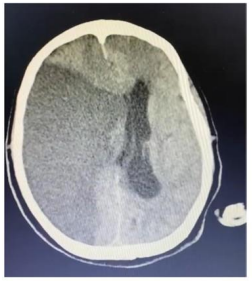

Um paciente de 76 anos de idade deu entrada na UPA, já fora de janela para trombólise, e foi posteriormente encaminhado para a UTI. A imagem apresentada refere-se à tomografia de admissão na UTI.

Com base na tomografia apresentada, assinale a alternativa que corresponde à artéria cerebral acometida e ao déficit esperado para o paciente